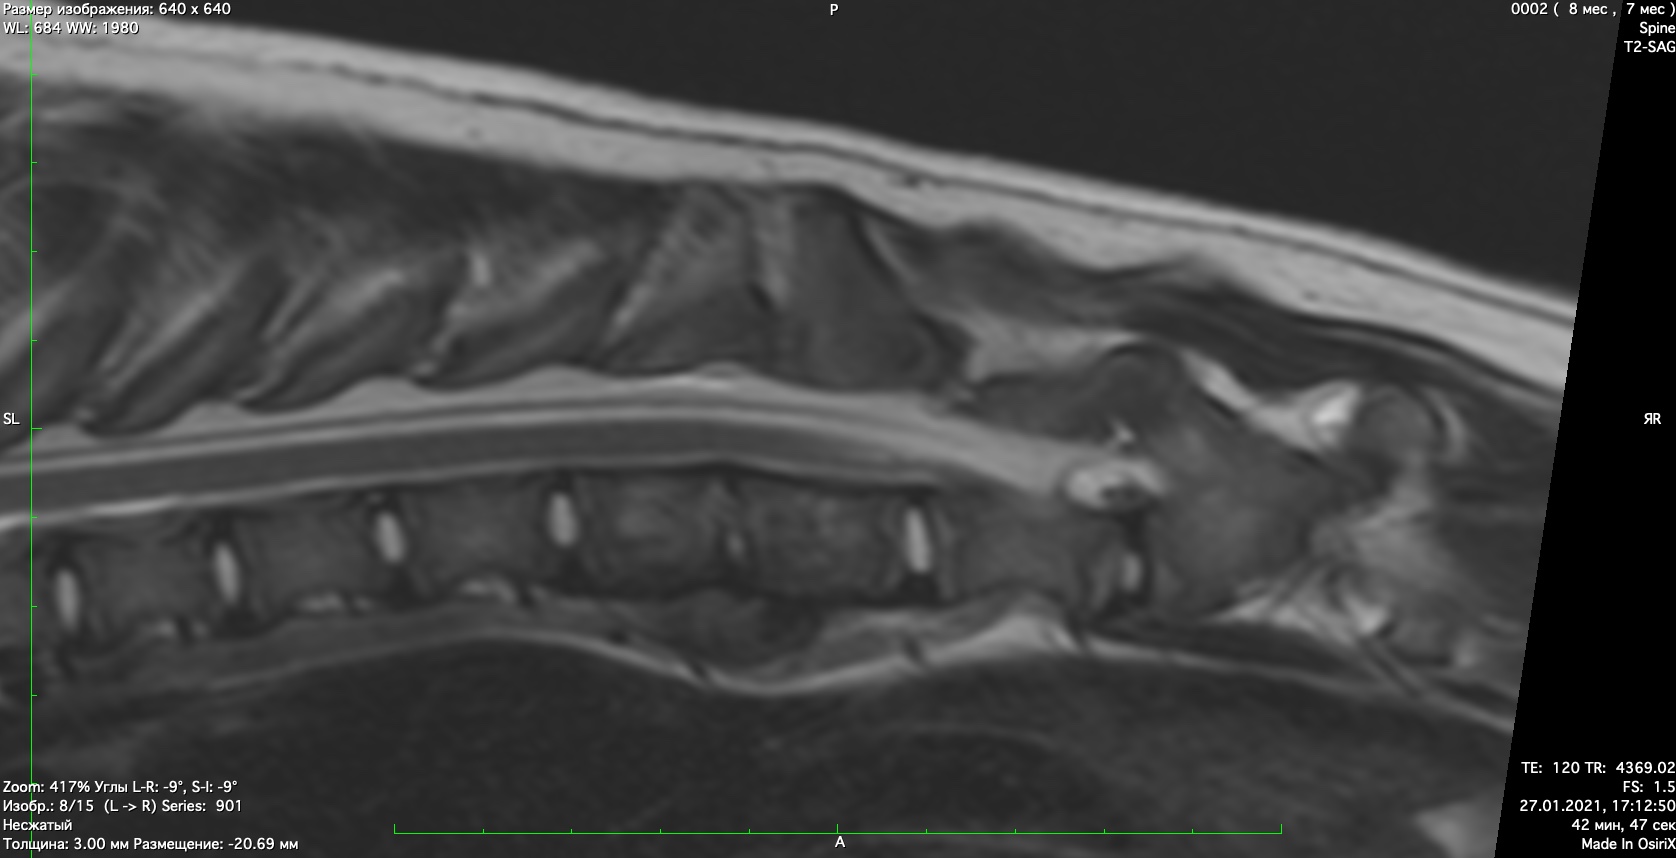

При проведении неврологического осмотра установлено- неврологический дефицит отсутствует, сильная болезненность при пальпации поясничного отдела позвоночника При проведении мрт диагностики установлено признаки воспаления позвонков поставлен диагноз-дискоспондиллит. начато лечение дискоспондиллита -антибиотиками